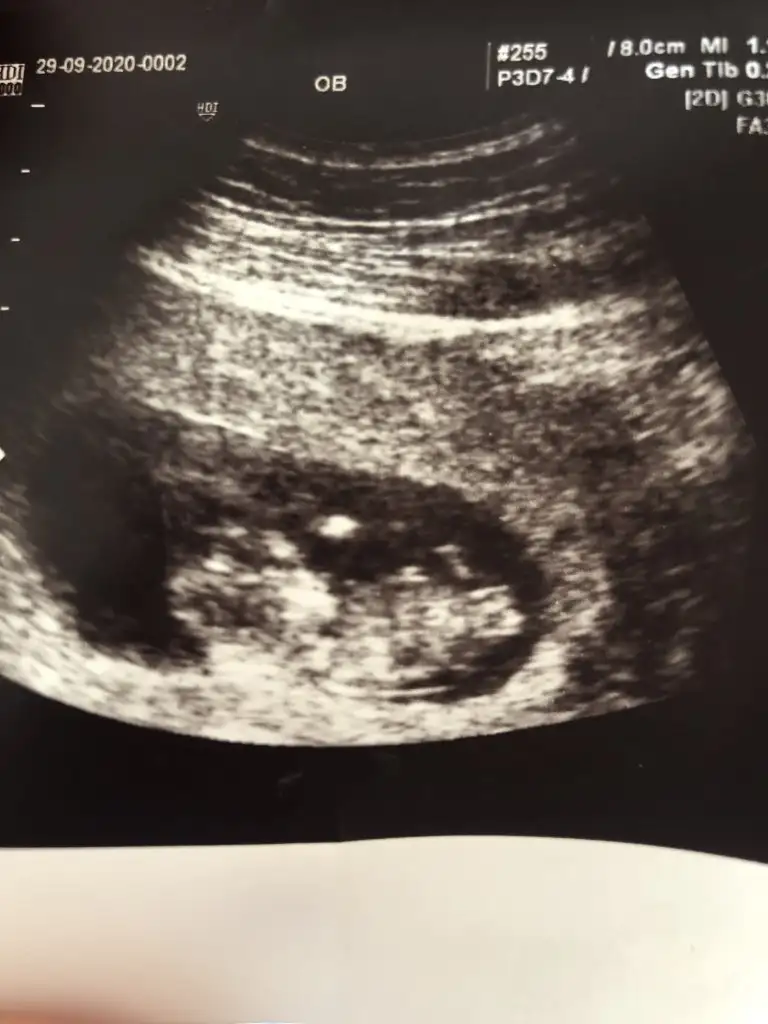

Evet biliyorum aynı usglerSiz daha önce kız demistinizhatta devlet hastanesi olunca net değil demiştim

Yanlış yere etiketlemisim Bu iste Mely15Banada tahminde buluna bilir misiniz acaba kizlar

Kaç haftalık büyük sanki USG 11 12 13 haftalar olmalı sanki sanki kız gibi tekrar USG paylasinBana da tahminde bulunabilir misiniz acaba